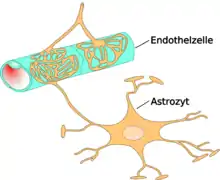

The blood-brain barrier (BBB) is one critical example of protection which prevents toxins and other adverse compounds from reaching the brain.[22] As the brain requires nutrient entry and waste removal, it is perfused by blood flow. Blood can carry a number of ingested toxins, however, which would induce significant neuron death if they reach nervous tissue. Thus, protective cells termed astrocytes surround the capillaries in the brain and absorb nutrients from the blood and subsequently transport them to the neurons, effectively isolating the brain from a number of potential chemical insults.[22]

This barrier creates a tight hydrophobic layer around the capillaries in the brain, inhibiting the transport of large or hydrophilic compounds. In addition to the BBB, the choroid plexus provides a layer of protection against toxin absorption in the brain. The choroid plexuses are vascularized layers of tissue found in the third, fourth, and lateral ventricles of the brain, which through the function of their ependymal cells, are responsible for the synthesis of cerebrospinal fluid (CSF).[23] Importantly, through selective passage of ions and nutrients and trapping heavy metals such as lead, the choroid plexuses maintain a strictly regulated environment which contains the brain and spinal cord.[22][23]

By being hydrophobic and small, or inhibiting astrocyte function, some compounds including certain neurotoxins are able to penetrate into the brain and induce significant damage. In modern times, scientists and physicians have been presented with the challenge of identifying and treating neurotoxins, which has resulted in a growing interest in both neurotoxicology research and clinical studies.[24] Though clinical neurotoxicology is largely a burgeoning field, extensive inroads have been made in the identification of many environmental neurotoxins leading to the classification of 750 to 1000 known potentially neurotoxic compounds.[21] Due to the critical importance of finding neurotoxins in common environments, specific protocols have been developed by the United States Environmental Protection Agency (EPA) for testing and determining neurotoxic effects of compounds (USEPA 1998). Additionally, in vitro systems have increased in use as they provide significant improvements over the more common in vivo systems of the past. Examples of improvements include tractable, uniform environments, and the elimination of contaminating effects of systemic metabolism.[24] In vitro systems, however, have presented problems as it has been difficult to properly replicate the complexities of the nervous system, such as the interactions between supporting astrocytes and neurons in creating the BBB.[25] To even further complicate the process of determining neurotoxins when testing in-vitro, neurotoxicity and cytotoxicity may be difficult to distinguish as exposing neurons directly to compounds may not be possible in-vivo, as it is in-vitro. Additionally, the response of cells to chemicals may not accurately convey a distinction between neurotoxins and cytotoxins, as symptoms like oxidative stress or skeletal modifications may occur in response to either.[26]